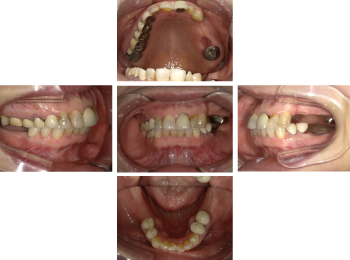

30代 女性 奥歯 インプラント

| 年代・性別 | 30代・女性 |

| 治療回数 | 10回(術前治療・検査除く) |

| 治療期間 | 約1年 |

| 料金 | ¥410,300(税込)※別途検査料 |

失った歯を補うために、インプラント治療は優れた治療方法です。 しかし、全ての人にインプラント治療が優れている治療ではありません。 |

| 副作用 | 術後に腫れ・痛みが出る可能性がある。 |